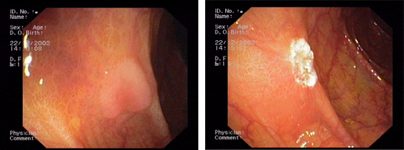

Endoscopic images:

imagen3

Multiple rectal ulcer